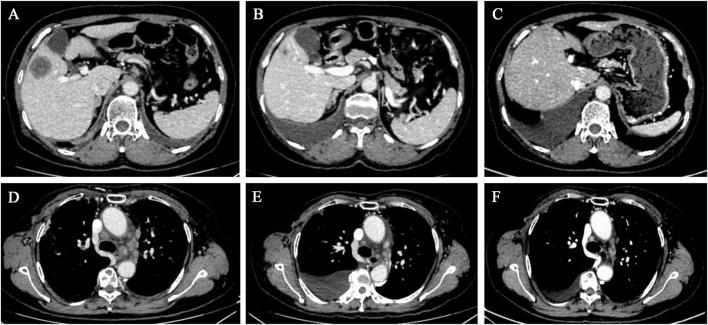

Trastuzumab deruxtecan (T-DXd or DS-8201), as a novel antibody-drug conjugate, has demonstrated good efficacy in HER2-positive advanced breast cancer. However, its effectiveness in treating pulmonary lymphangitic carcinomatosis (PLC) has not been previously reported. This paper presents a case of a HER2-positive advanced breast cancer patient who experienced disease progression after treatment with trastuzumab and pertuzumab. The patient developed multiple metastases along with PLC and subsequently received T-DXd treatment, achieving 14.2 months of progression-free survival (PFS). This case is the first to reveal the therapeutic potential of T-DXd in breast cancer patients with PLC.

曲妥珠单抗德曲妥珠单抗(T-DXd或DS-8201)作为一种新型抗体药物偶联物,已在HER2阳性晚期乳腺癌中显示出良好疗效。然而,其治疗肺淋巴管癌病(PLC)的有效性此前尚未见报道。本文介绍了1例HER2阳性晚期乳腺癌患者,该患者在接受曲妥珠单抗和帕妥珠单抗治疗后病情进展。患者出现多处转移并伴有PLC,随后接受T-DXd治疗,无进展生存期(PFS)达14.2个月。该病例首次揭示了T-DXd在伴有PLC的乳腺癌患者中的治疗潜力。